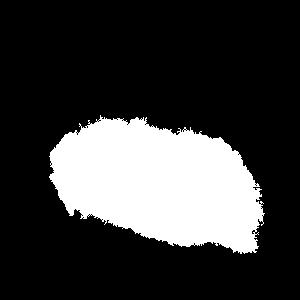

Figure 2a. illustrates the information retrieved from this CNN model from various layers of the architecture that is used to create a BAM map, which is used to segment the burn injury from normal skin in a 2D image. First, the heatmaps for the activations of the first convolutional layer are computed (Figure 2a(ii)), and then Grad-CAM heatmap is computed using the last convolutional layer (Figure 2a(iii)). Once the first convolutional layer heatmaps and Grad-CAM are generated, the algorithm uses a three-round iterative process to select activation heatmaps that have the highest correlation to the Grad-CAM heatmap among the channels of the first layer activations. After the process of correlating and selecting heatmaps is completed (Figure 3 ), segmentation masks are created next (Figure 4). A final composite BAM mask is created as illustrated in 2b(i). Finally, figure 2b (ii-iii) illustrates how the BAM mask is superimposed on the input image to segment the burn injury area, and how edge detection may be applied to the BAM mask in order to obtain a fine-tuned segmented boundary superimposed on the input image.

Once the heatmaps with the highest correlation coefficients are selected, these high-resolution visualizations are utilized as the input to make binary segmentation masks as illustrated in Figure 4(i). The generation of masks uses Gaussian components of the maps to find thresholds (Figure 4(ii)) and subsequently uses the highest Intersection-Over-Union (IOU) values (Figure 4(iii)) between the binary masks generated and the Grad-CAM to select the final mask. The generated binary segmentation mask lastly undergoes a post-processing step in order to filter out the noise/false positive regions and produce the final BAM mask (Figure 4(iv)), which can be used for super-positioning on the input image (Figure 2b).

Figure 5 shows several burn image examples of patients with different sized burns in different body locations, for which the Grad-CAM heatmap, BAM heatmap, BAM masks, and final superimposed images were created. These results allow us to understand the clinical accuracy of burn segmentation from 2D images using BAM. These images show various degrees of burn. It is evident from the results that given skin burn images and the corresponding Grad-CAM heatmaps highlighting the burn regions even partially, the BAM heatmap is able to highlight the burn regions and display a high resolution heatmap accurately. This is the main contribution of BAM. It can be seen from the figure that the BAM heatmaps display different contrast levels in highlighting the burn regions. More precisely, the more superficial burns are highlighted with a lower contrast to the normal skin. The deeper burns, on the other hand, are highlighted with a higher contrast to the normal skin. Nevertheless, the contrast between the burn regions and the normal skin in the BAM heatmaps is sufficient for generating the binary segmentation masks even for the more superficial burns. As evidenced, the BAM heatmaps can successfully be converted into accurate binary segmentation masks. The rightmost column of the figure shows the BAM segmentation masks on top of the input images in order to better visualize the effectiveness of BAM in segmenting the burn regions. In short, comparing the Grad-CAM heatmaps against the BAM heatmaps and BAM segmentation masks provides evidence for a significant improvement in generating heatmaps that are both class-discriminative and fine-grained.